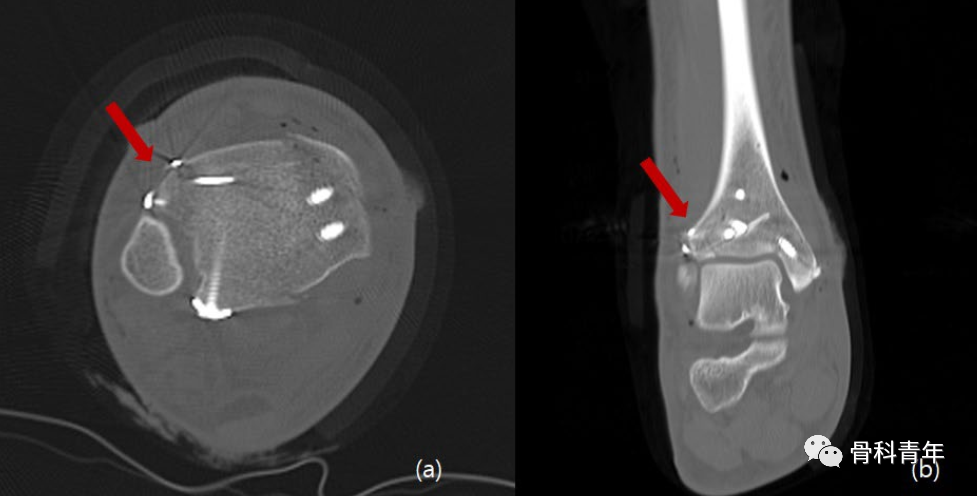

Chaput结节骨折在旋转型踝关节骨折中较为常见,距骨外旋挤压外踝,导致下胫腓韧带损伤或下经下胫腓韧带止点的撕脱骨折,胫骨止点的撕脱为Chaput结节骨折,亦称“前踝骨折”,外踝止点的撕脱骨折即为Wagstaff结节骨折。螺钉固定时最主流的固定方法,但该方法需要骨块足够大并较为完整,否则螺钉置入后存在骨块碎裂风险;对较为粉碎的Chaput结节骨折,推荐一期小钢板内固定。

也有学者采用锚钉固定,将骨块通过锚钉缝线固定于胫骨远端,但该方法的总体固定强度不如内固定。考虑到张力带原则在腱-骨连接处骨折中的广泛应用,如髌骨、内踝等,有研究人员开始采用克氏针张力带技术固定Chaput骨块: